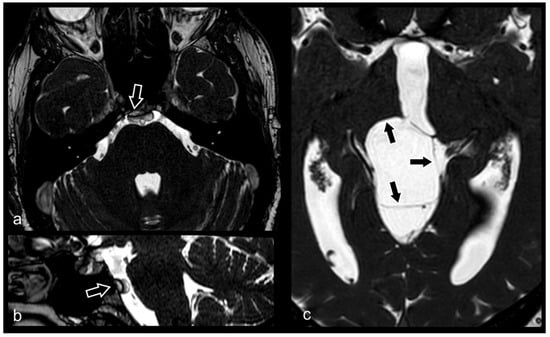

3.1.4. Trigeminal Nerve (V)

3.4. Cerebrovascular Pathology

3.11. Evaluation of Internal Auditory Canal and Inner Ear Structures